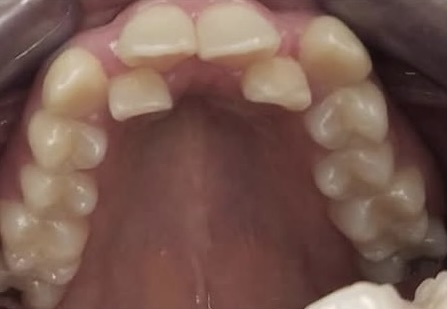

Crowding and constricted arch. Comprehensive orthodontic treatment was performed, and teeth alignment was restored.